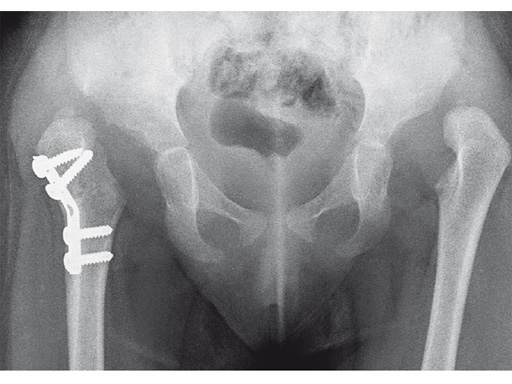

An 18-month old girl presented with developmental dysplasia of the hip. She had failed conservative management with a Pavlik harness, and redislocated following open reduction and femoral osteotomy of the right hip. She underwent revision open reduction and femoral osteotomy of the right hip, followed by the same procedure on the left hip 6 weeks later.

Case provided by James B Hunter, Nottingham, UK